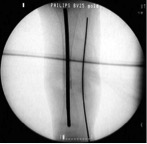

(Biz drilleme ve osteotomi tekniğini tercih etmekteyiz. Osile eden testereler ısıya bağlı osteonekroz oluşturup kaynamayı engelleyebileceğinden tercih edilmemelidir). Fibular psödartroz da varsa aynı işlem aynı ensizyondan uygulanmalıdır. Rezeksiyon sonrası tibia ve fibula yaklaşık1-2 cm kısaltılmış olur. Turnike açılır ve kemik uçlarının canlılığı (paprika sign) görülür. Daha önce ölçülerek uzunluğu hazırlanmış Steinmann çivisi (ya da İM rod) rezeksiyon sahasından intramedüller olarak yerleştirilir.

Hemostazı takiben katlar anatomik olarak kapatılmalıdır. Daha önceden hazırlanmış 3 halkadan oluşan sirküler eksternal fiksatör K-telleri ile frontal ve sagittal planlarda anatomik eksene paralel olarak yerleştirilmelidir. Burada dikkat edilmesi gereken fiksatörün K-telleri ile Steinmann çivisi temas etmemelidir. Proksimal tibia’dan fizise çok yakın kortikotomi ile mevcut kısalık da rekonstrukte edilir.